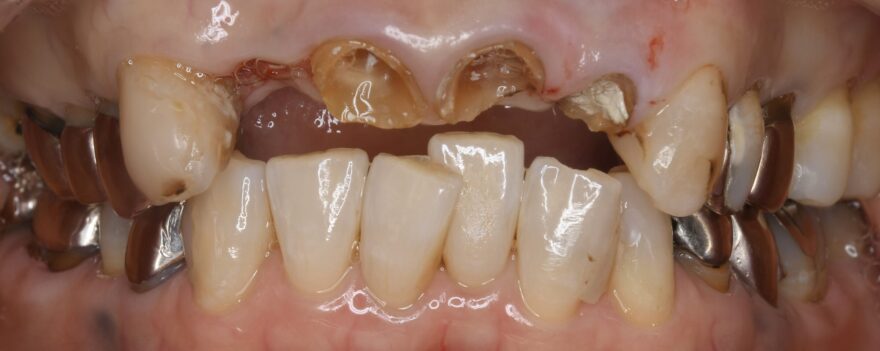

初診時の口腔内写真